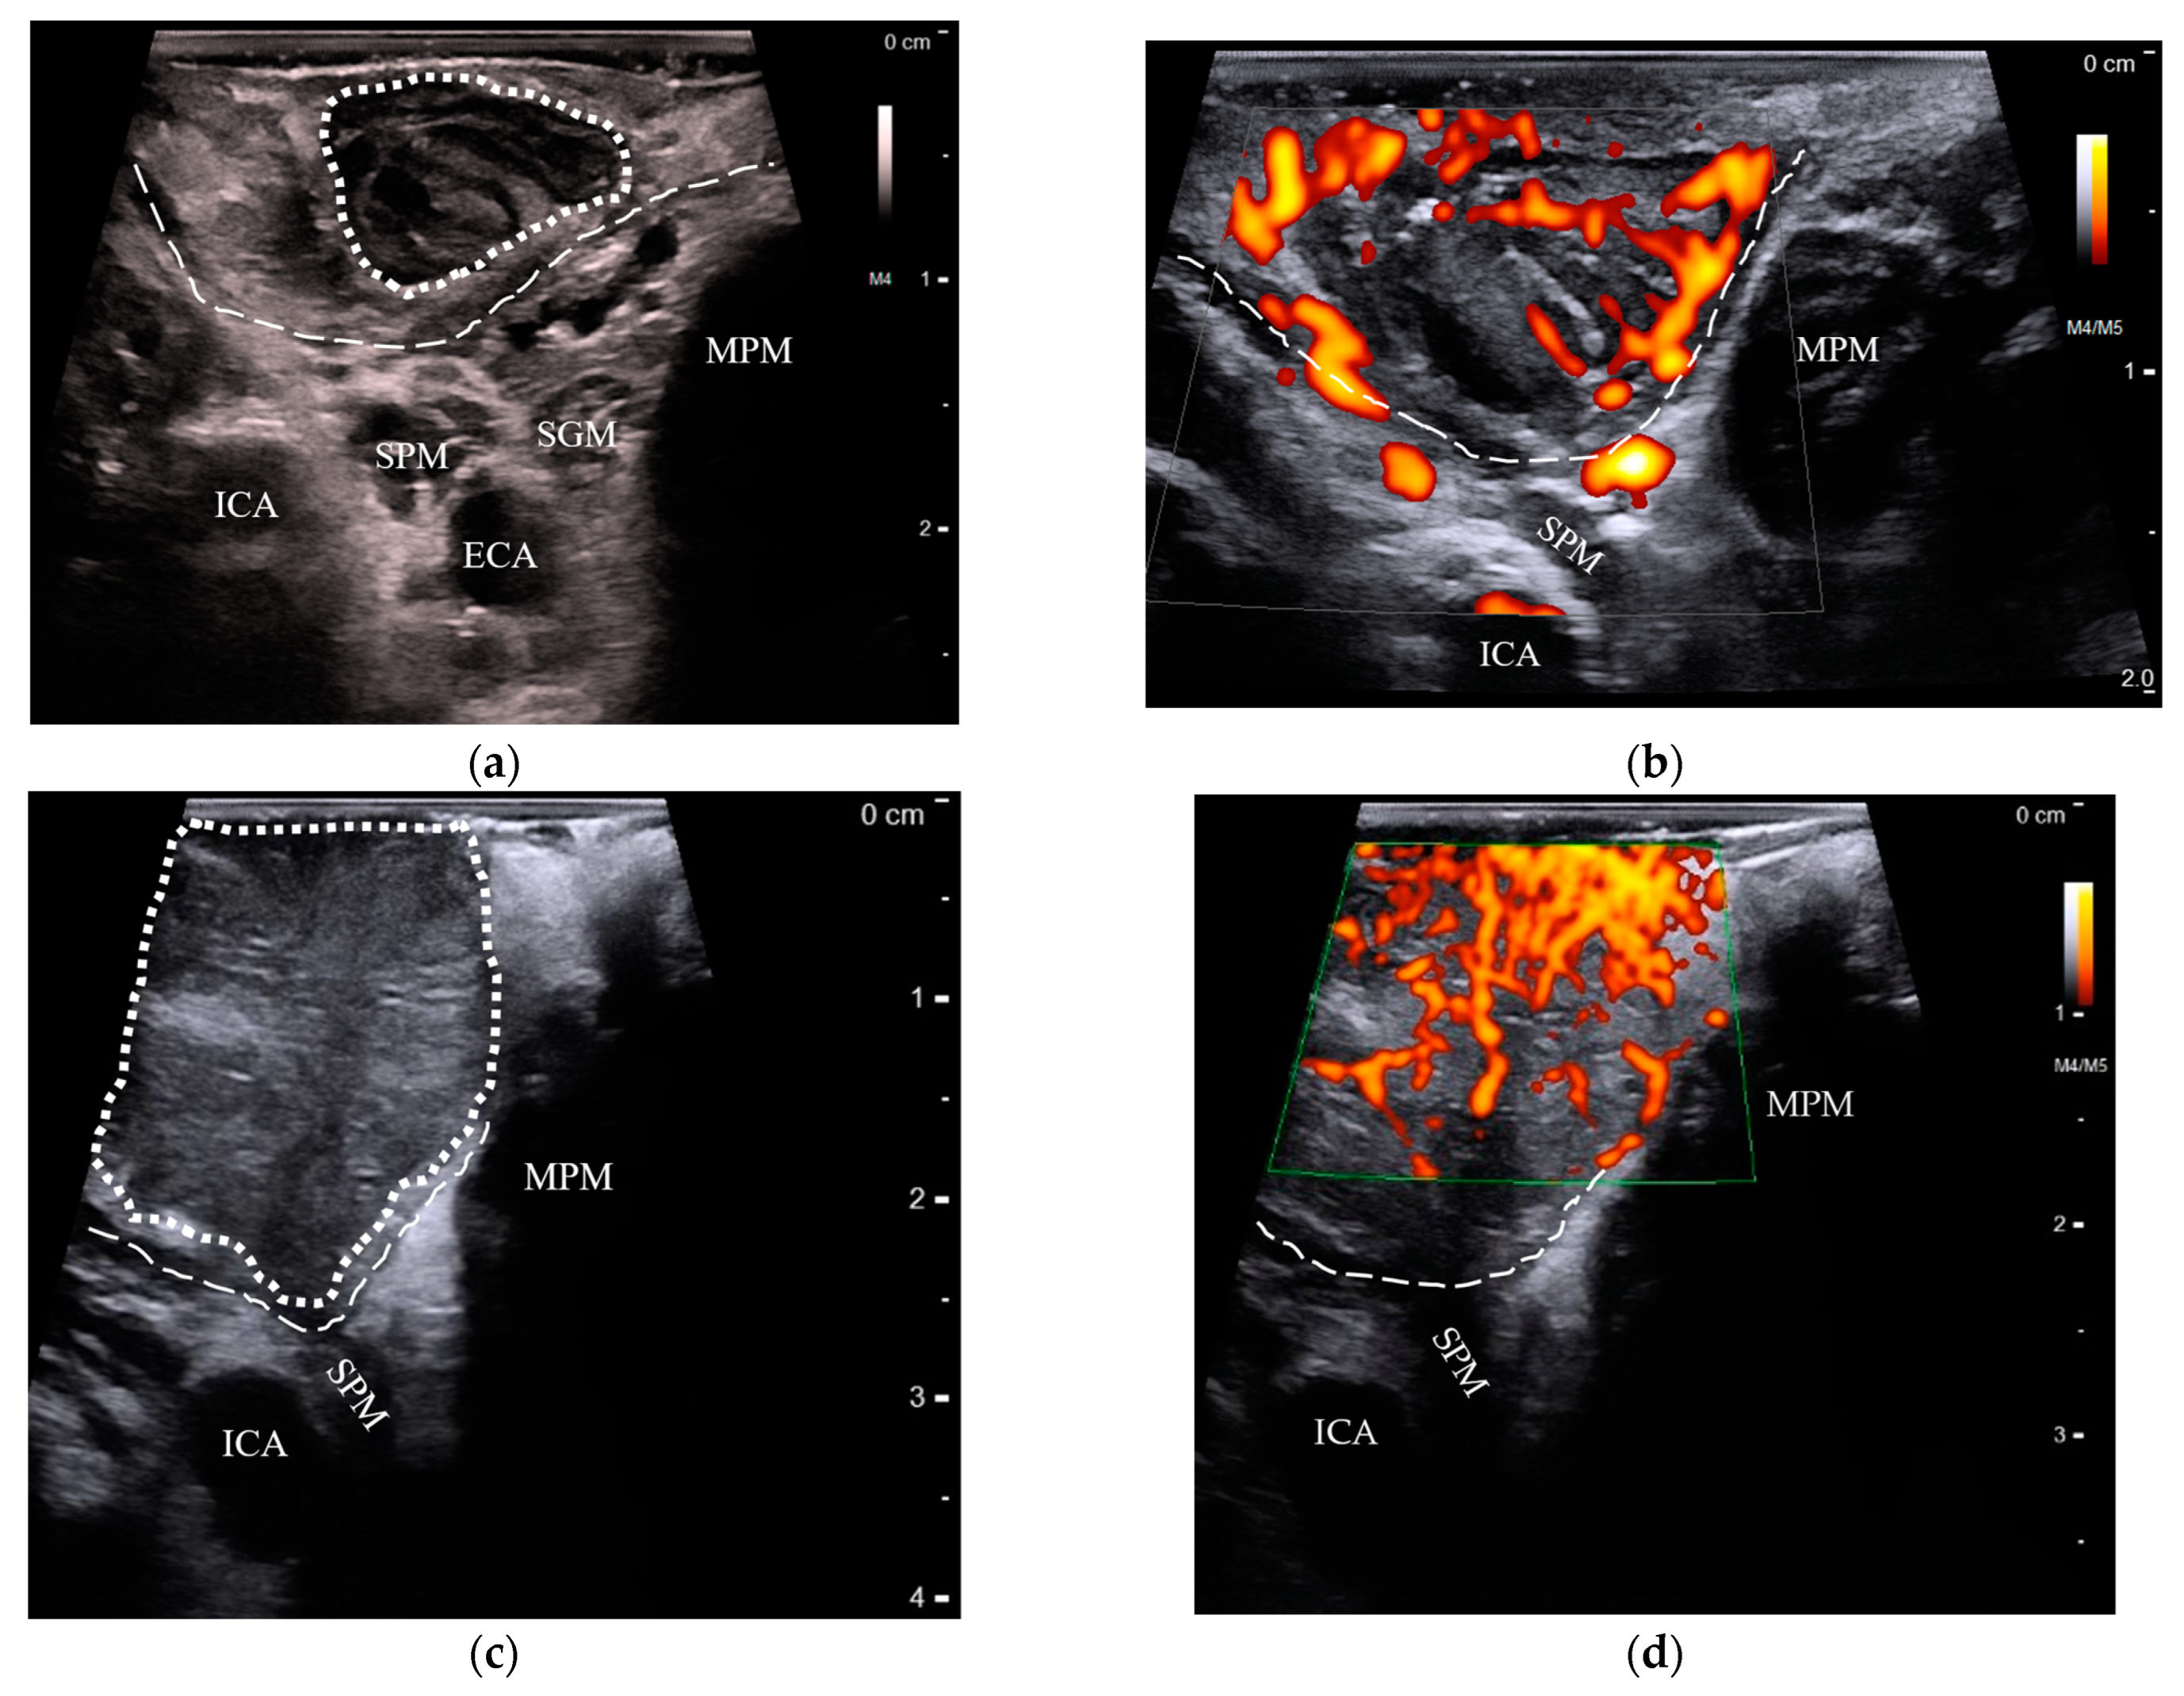

3.3. Detection of OPCs Compared between US and MRI

3.4. Comparison of T-Staging between US and MRI

3.4.1. Correlation of the Greatest Tumor Size